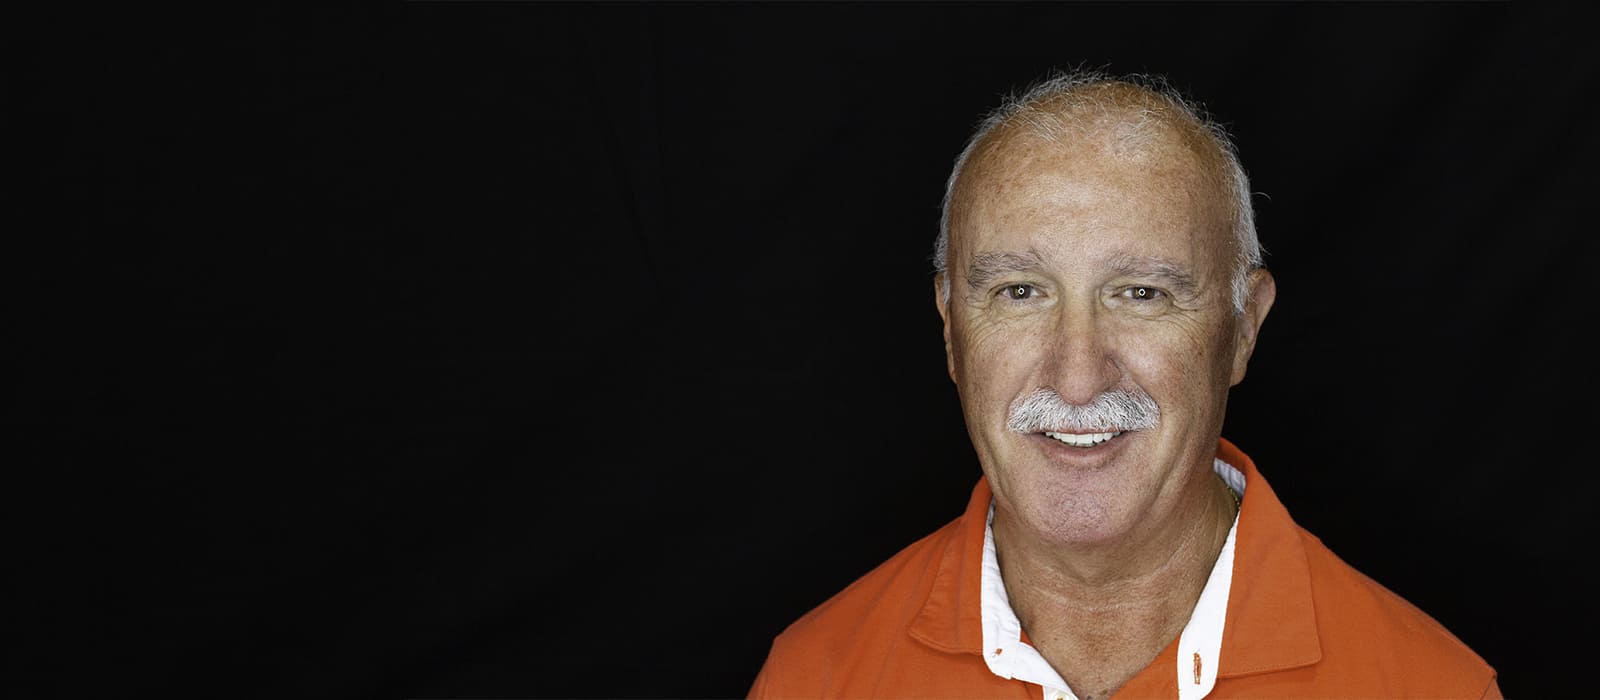

Jacinto

Jacinto vino a Ferrus & Bratos con una situación compleja: mostraba un número importante de ausencias dentarias, y las piezas dentales que permanecían en su boca presentaban fracturas, extensas lesiones cariosas y pérdida de soporte periodontal.

Analizando su caso, le propusimos una rehabilitación completa de la arcada superior con una prótesis híbrida sobre implantes. Con este plan de tratamiento queríamos alcanzar tres objetivos: mejorar su salud bucodental, facilitar el proceso de masticación y conseguir una oclusión perfecta y, por último, lograr un cambio significativo a nivel estético.

Jacinto aceptó el reto, animado por su mujer -también paciente de Ferrus & Bratos-. Ahora ya ha terminado el tratamiento, y dice notar grandes mejoras a la hora de comer y sentirse mucho más seguro de sí mismo con su nueva sonrisa.